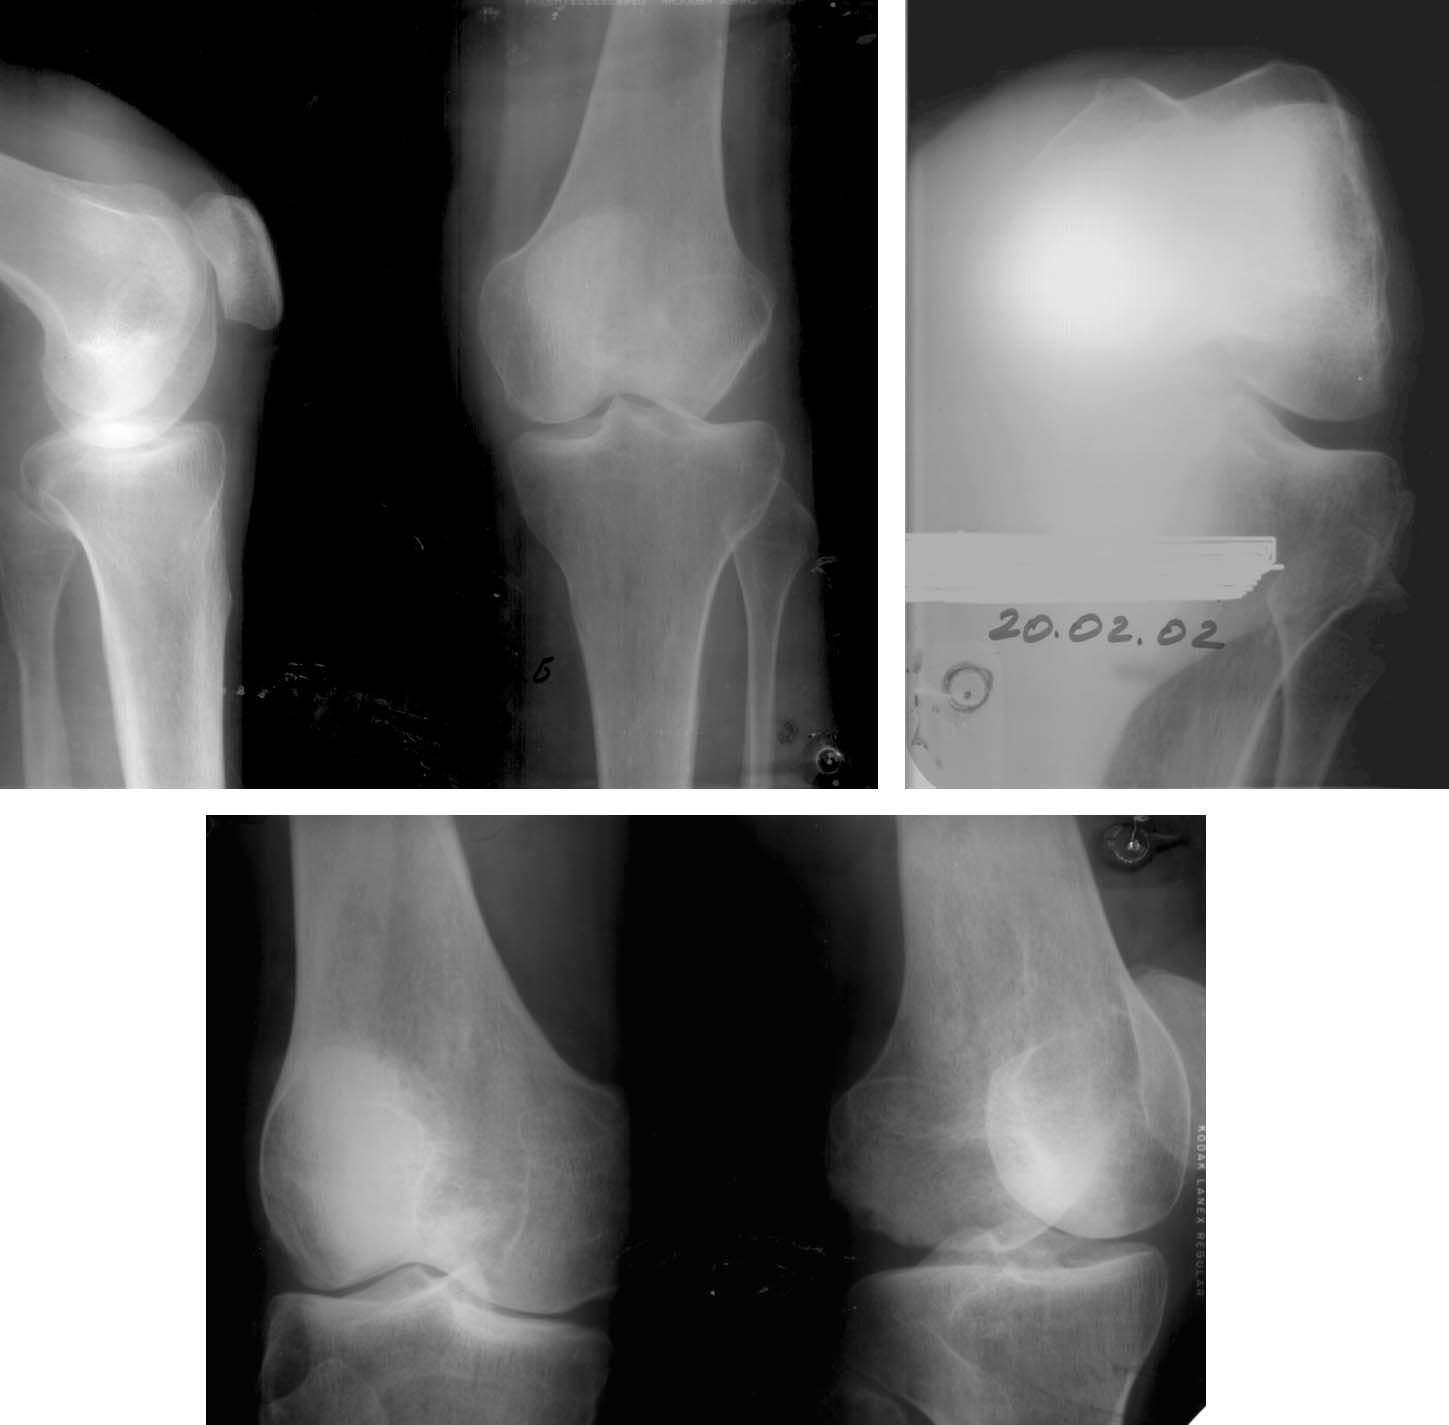

Женщина, 32 года.Травма в ДТП 24.05.01Диагноз: Политравма (разрыв лонного и правого крестцово-подвздошного сочленения, разрыв мочевого пузыря, вывих правого плеча, переломы пальцев кисти, носа, закрытая черепно-мозговая травма, обширные раны левого коленного сустава).Прошла хирургическое лечение. Больная активизирована, поставлена на костыли, обучена ходьбе. С целью стабилизации левого коленного сустава и удержание левой стопы использовался индивидуальный ортез.В настоящее время - посттравматический дефект наружного мыщелка левой бедренной кости. На рентгенограммах левого коленного сустава в укладках определяется дефект наружного мыщелка бедренной кости до 1/3 суставной поверхности. При клиническом обследовании левого коленного сустава: умеренная гипотрофия мышц левого бедра и голени, при пальпации проекции суставной щели снаружи умеренная болезненность, при выполнении клинических проб отмечается патологическая девиация голени кнаружи до 20 градусов, сопровождающаяся появлением умеренной боли, движения в коленном суставе незначительно ограничены.Вопрос: лечение дефекта?

Я позволил себе проконсультировать присланные Вами Rg в отделе РосНИИТО, специализирущемся на патологии коленного сустава. Действительно, пациенты с травматическими дефектами части мыщелка бедренной кости являются "штучными"

и об отработанной технологии здесь говорить не приходится. Однако определенный опыт и подходы к решению данной проблемы есть. Курирует эти

вопросы у нас в.н.с. Засульский Филипп Юрьевич. Если считаете целесообразным, Вы можете связаться с ним: Herihor@rambler.ru